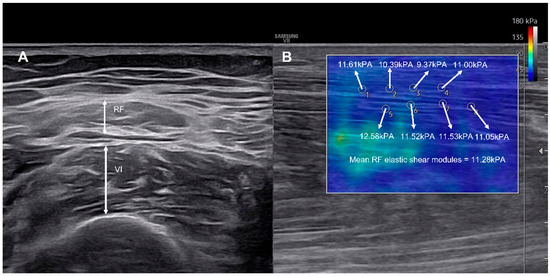

Association Between Electrophysiological Evaluation and Muscle Quality Changes in the Lower Limb of Subacute Stroke Patients: A Pilot Longitudinal Observational Study

by Se Jin Kim, Jeong Hwan Lee, Young Sook Park, Hyun Jung Chang, Jin Gee Park, Eun Sol Cho, Jae Yeon Kim and Dong Jin Ha

Background: This pilot longitudinal observational study investigated 4-week changes in lower limb muscle quantity and quality in patients with subacute stroke and explored risk factors associated with these changes. Methods: Twenty-six patients with hemiplegia following subacute stroke underwent assessment at baseline and 4-week follow-up. Muscle quantity was evaluated by ultrasound muscle thickness and bioelectrical impedance analysis, while muscle quality was assessed by shear-wave elastography in seven muscles (rectus femoris, vastus intermedius, vastus lateralis [VL], vastus medialis, tibialis anterior, gastrocnemius [GCM], and soleus). Electrophysiological assessments included motor-evoked potential (MEP), somatosensory-evoked potential (SEP), nerve conduction studies (NCSs), and central motor conduction time (CMCT). Results: Muscle thickness and bioimpedance did not significantly change between baseline and follow-up. In contrast, shear modulus increased in the paretic-side VL and GCM muscles (p < 0.001 and p = 0.049), with no differences in the non-paretic side. Greater deterioration in GCM quality was observed in patients with abnormal lower-limb MEP, and increased VL stiffness correlated with prolonged CMCT. Multivariable analyses were performed adjusting for age, sex, National Institutes of Health Stroke Scale, and comorbidity burden; however, due to the small electrophysiology sample (n = 11), these results should be interpreted as exploratory. Conclusions: In subacute stroke, early deterioration in muscle quality can occur despite stable quantity and appears linked to corticospinal integrity. Integrating electrophysiological evaluation with elastography may help identify patients who could benefit from early, targeted neuromuscular rehabilitation. These exploratory findings require validation in larger cohorts. Full article

Figure 1